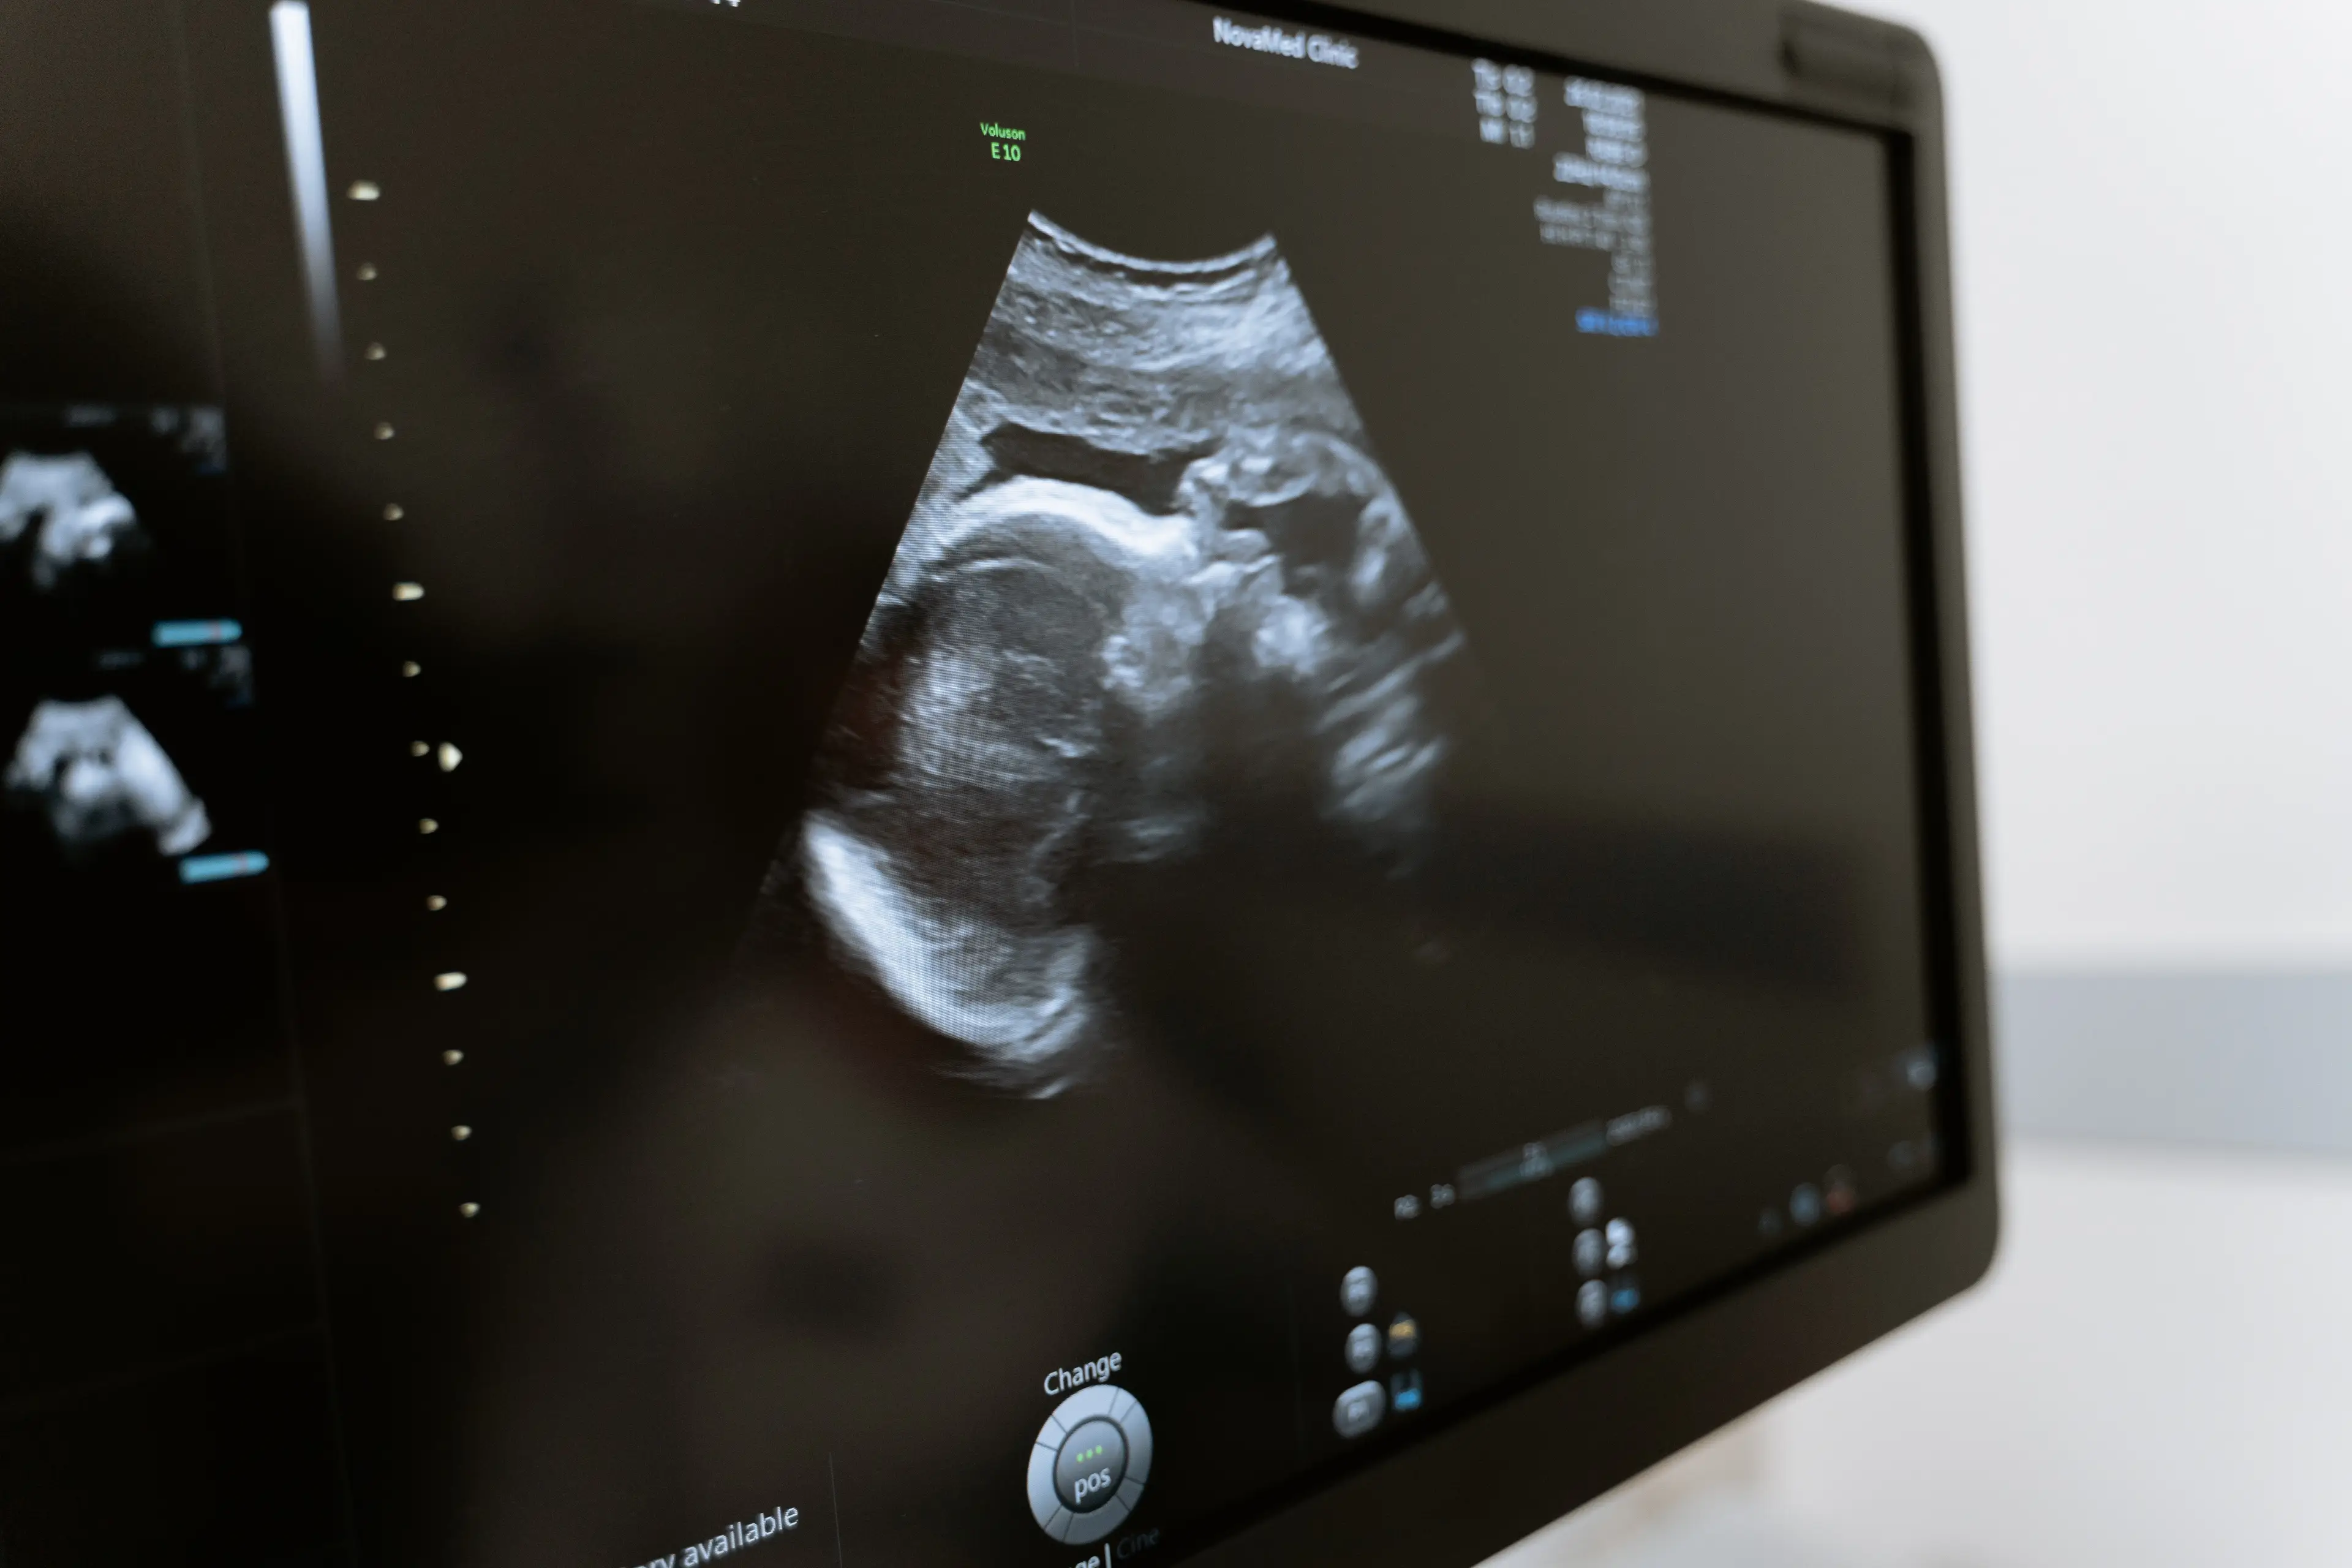

Doctors used ultrasound technology to help guide them during the surgery, which was carried out while the mother was 34-weeks pregnant.